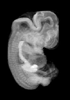

Carnegie Stage 19 (47 post-ovulatory days)

Most embryos at stage 19 are approximately 47-48 post-ovulatory days old and measure 17-20 mm in length. Distinguishing criteria for this stage include straightening of the trunk, the limbs extend nearly directly forward, toe rays are prominent, but interdigital notches have not yet appeared in the foot.

MRI Slice Selector

Mouse: click on a line below to select a view

Finger: tap a line below with a very light touch